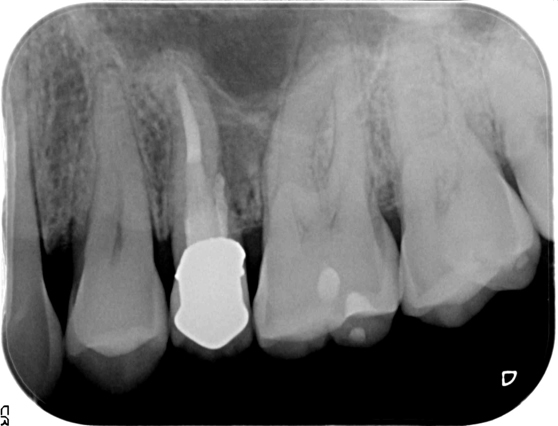

歯根端切除術

歯根端切除術は、歯根の先端の感染源を切り取り、薬を詰める治療法です。通常の根管治療だけでは治らない場合・何らかの理由で通常の根管治療が行えない場合に行います。